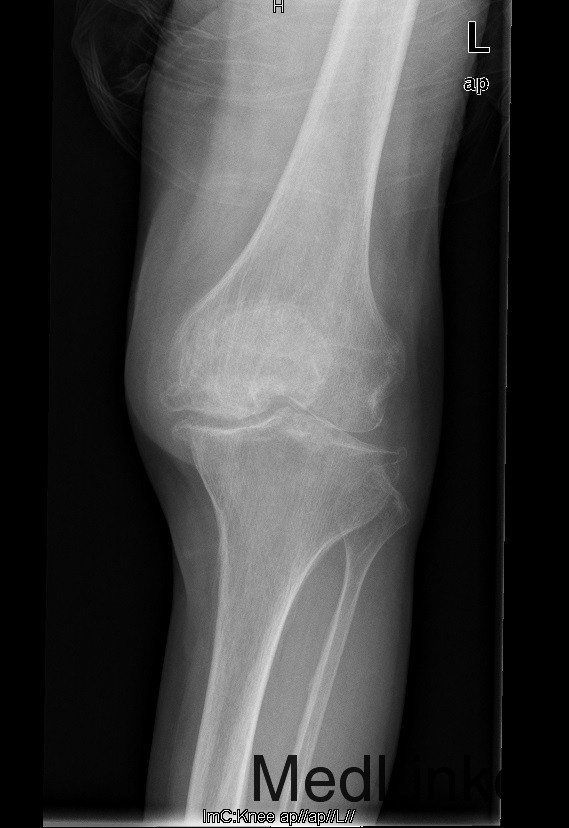

查体:跛行步态,左侧股内侧肌萎缩,左膝内侧关节间隙压痛,左膝髌股关节间隙压痛。左膝伸-45°,屈90°,左膝屈伸活动时髌骨下摩擦感 (+)。 辅助检查:左髌股关节内侧间室变窄,关节边缘骨赘增生,软骨下骨硬化

诊断:1、左膝骨关节炎伴屈曲畸形 2、左髌骨骨折骨愈合 治疗:积极行术前准备后于全麻下行左侧全膝关节置换术+软组织松解术,术后常规治疗。